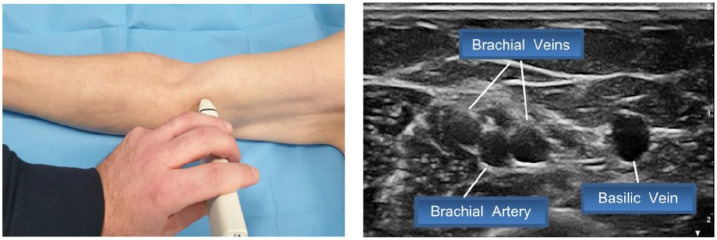

外周置入中心导管(PICC)的插入可能会带来直接/早期不良事件的风险,其中有些风险很小(重复穿刺),有些则很严重(意外动脉穿刺或神经相关损伤)。在插入过程中采取的几种策略可将此类事件的风险降至最低,包括感染、静脉血栓或导管脱落和/或错位等后期并发症风险。本文介绍了 SIP 协议(PICC 安全插入)的更新版本,该插入捆绑包包括八种有效策略,旨在最大限度地减少与插入相关的即时、早期或晚期并发症。这些策略包括:利用 RaPeVA(快速外周静脉评估)方案进行术前超声评估;适当的皮肤消毒技术;选择适当的静脉,采用 Zone Insertion Method™(区域插入法);明确识别正中神经和肱动脉;超声引导下穿刺;超声引导下的尖端导航;术中评估尖端位置;正确固定导管以及适当保护出口部位。这一更新版 SIP 方案包括几项基于 PICC 插入最新循证科学文献的新技术,如隧道技术的临床实用性、术中尖端导航和尖端位置超声的使用,以及出口部位保护(氰基丙烯酸酯胶)和导管固定(皮下固定)的新技术。

Insertion of Peripherally Inserted Central Catheters (PICCs) is potentially associated with the risk of immediate/early adverse events, some of them minimal (repeated punctures) and some relevant (accidental arterial puncture or nerve-related injury). Several strategies adopted during the insertion process may minimize the risk of such events, including late complication risks such as infection, venous thrombosis, or catheter dislodgment and/or malposition. This paper describes an update version of the SIP protocol (Safe Insertion of PICCs), an insertion bundle which includes eight effective strategies that aims to minimize immediate, early, or late insertion-associated complications. These strategies include: preprocedural ultrasound assessment utilizing the RaPeVA (Rapid Peripheral Venous Assessment) protocol; appropriate skin antiseptic technique; choice of appropriate vein, adoption of the Zone Insertion Method™; clear identification of the median nerve and brachial artery; ultrasound-guided puncture; ultrasound-guided tip navigation; intra-procedural assessment of tip location; correct securement of the catheter, and appropriate protection of the exit site. This updated version of the SIP protocol includes several novelties based on the most recent evidence-based scientific literature on PICC insertion, such as the clinical relevance of the tunneling technique, the use of ultrasound for intra-procedural tip navigation and tip location, and the new technologies for the protection of the exit site (cyanoacrylate glue) and for the securement of the catheter (subcutaneous anchorage).